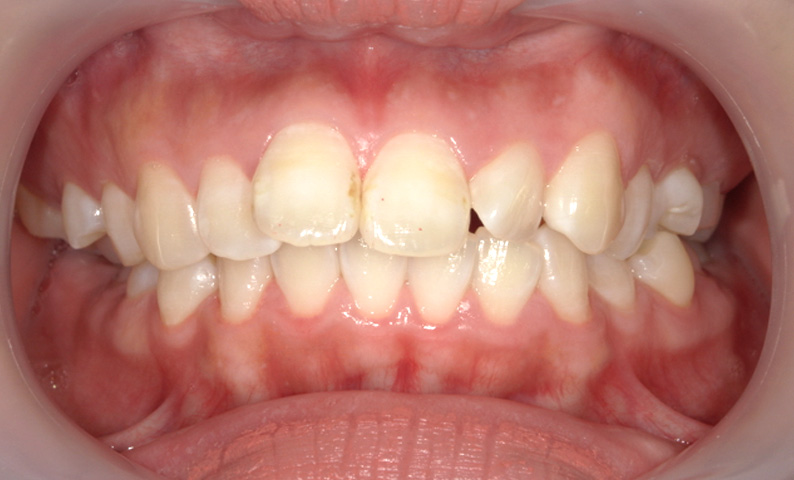

症例_010 「出っ歯」症例

治療期間:7ヶ月金額:30万円+税20代女性出っ歯捻転歯上の前歯だけ

| Before | After |